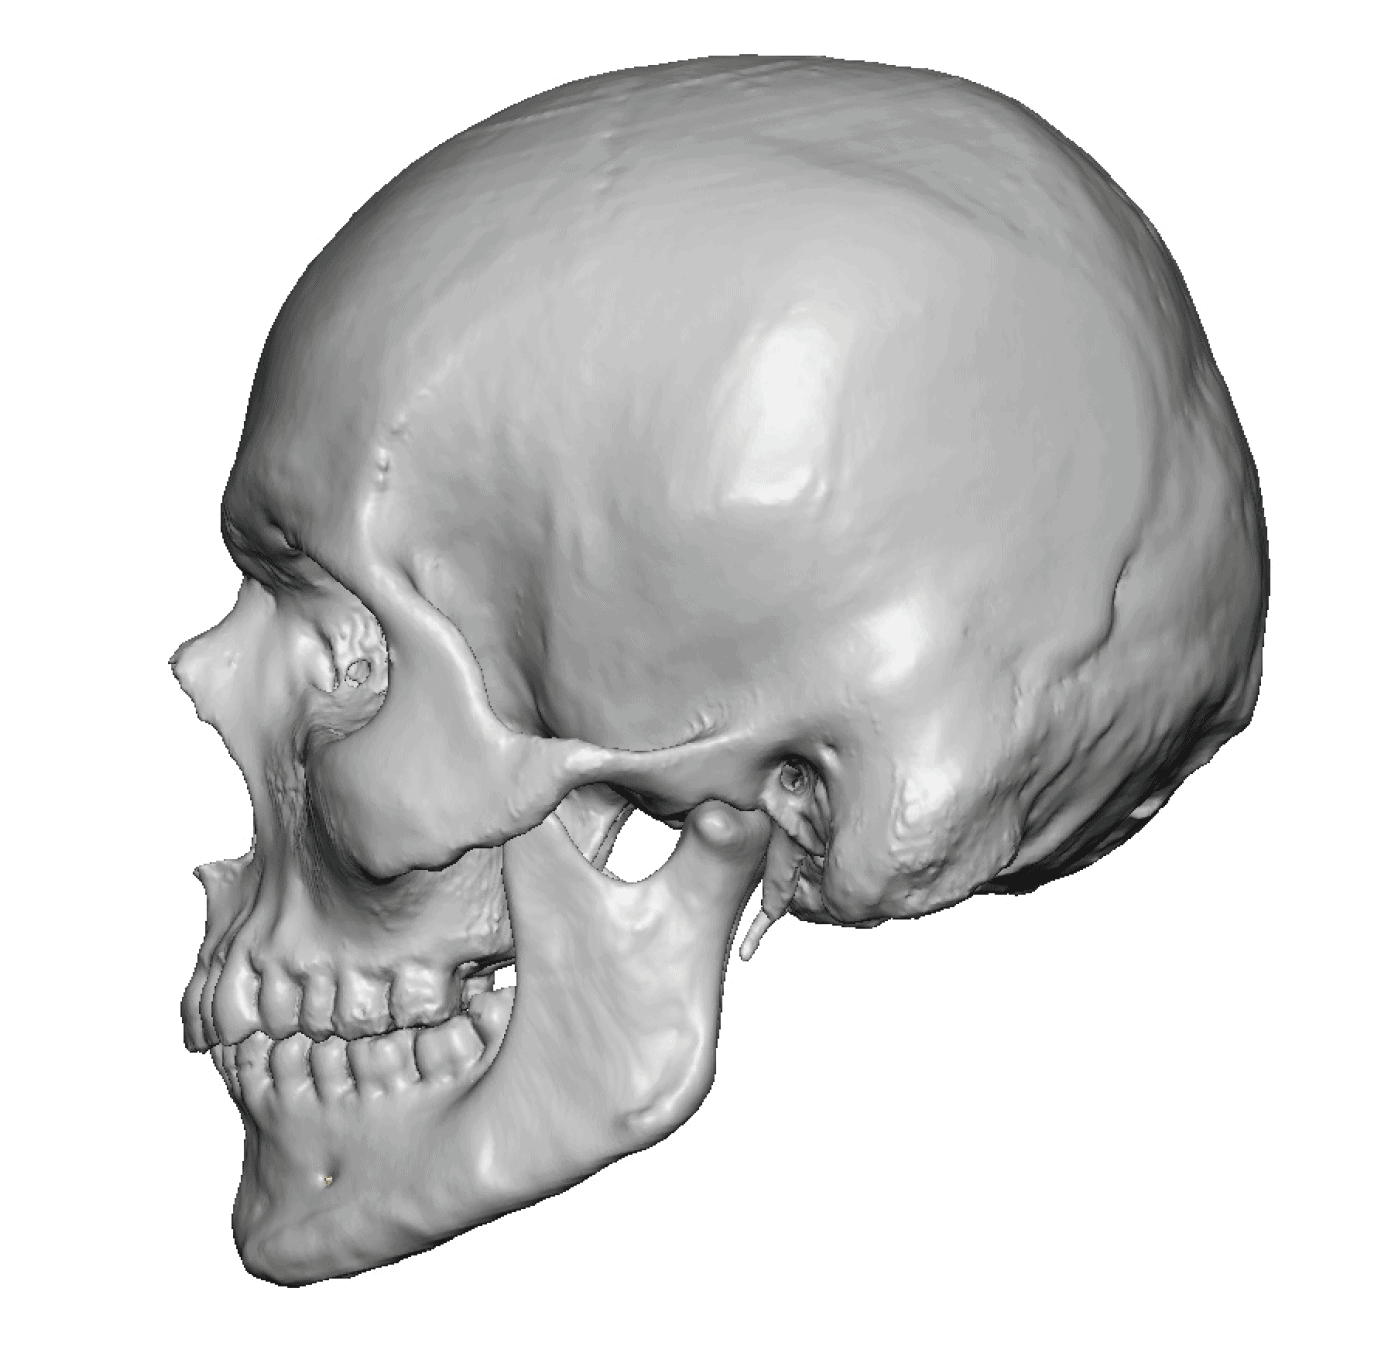

Desire for a higher and more prominent crown of the skull.

Crown of skull augmentation using a custom skull implant.

Desire for a higher and more prominent crown of the skull.

Crown of skull augmentation using a custom skull implant.